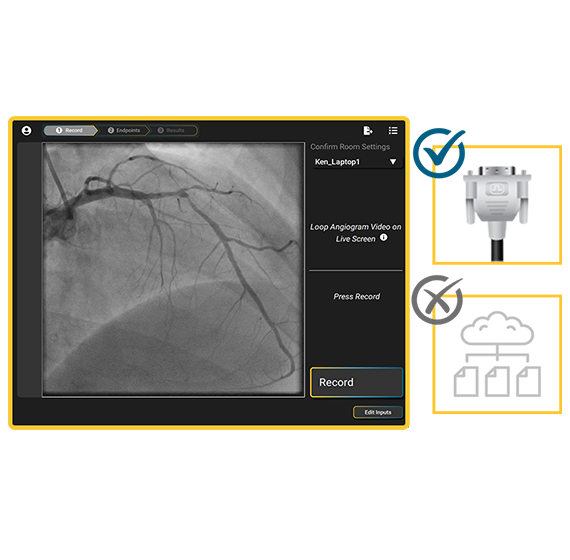

Seamless Angio Acquisition

Direct feed from angiography system removes the need for network-based DICOM file collection, management and review